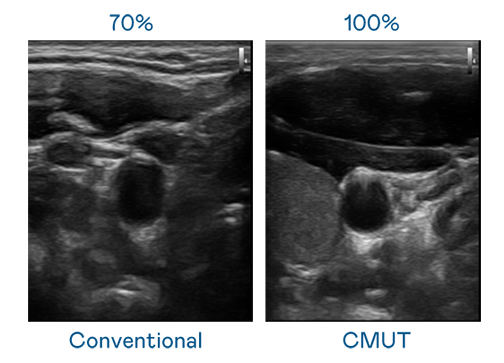

CMUT 技术是一种用电容式微机电元件来产生超音波讯号的技术。与传统 PZT 压电式技术相比,CMUT 频宽增加 30%,更宽频的超音波讯号让影像解析度大幅提升,是实现高影像品质医疗超音波扫描、促进精准医疗发展的关键技术。

大频宽带来超清晰影像

超音波影像的解析度高低,首先取决于探头能发出的讯号频宽。乐竞app官方下载入口 CMUT 可提供高清晰的超音波讯号,提供高频宽、高灵敏度、影像纹理细节更高的超音波影像,协助医护人员缩短影像判读时间及利用精准的医疗影像进行诊断。